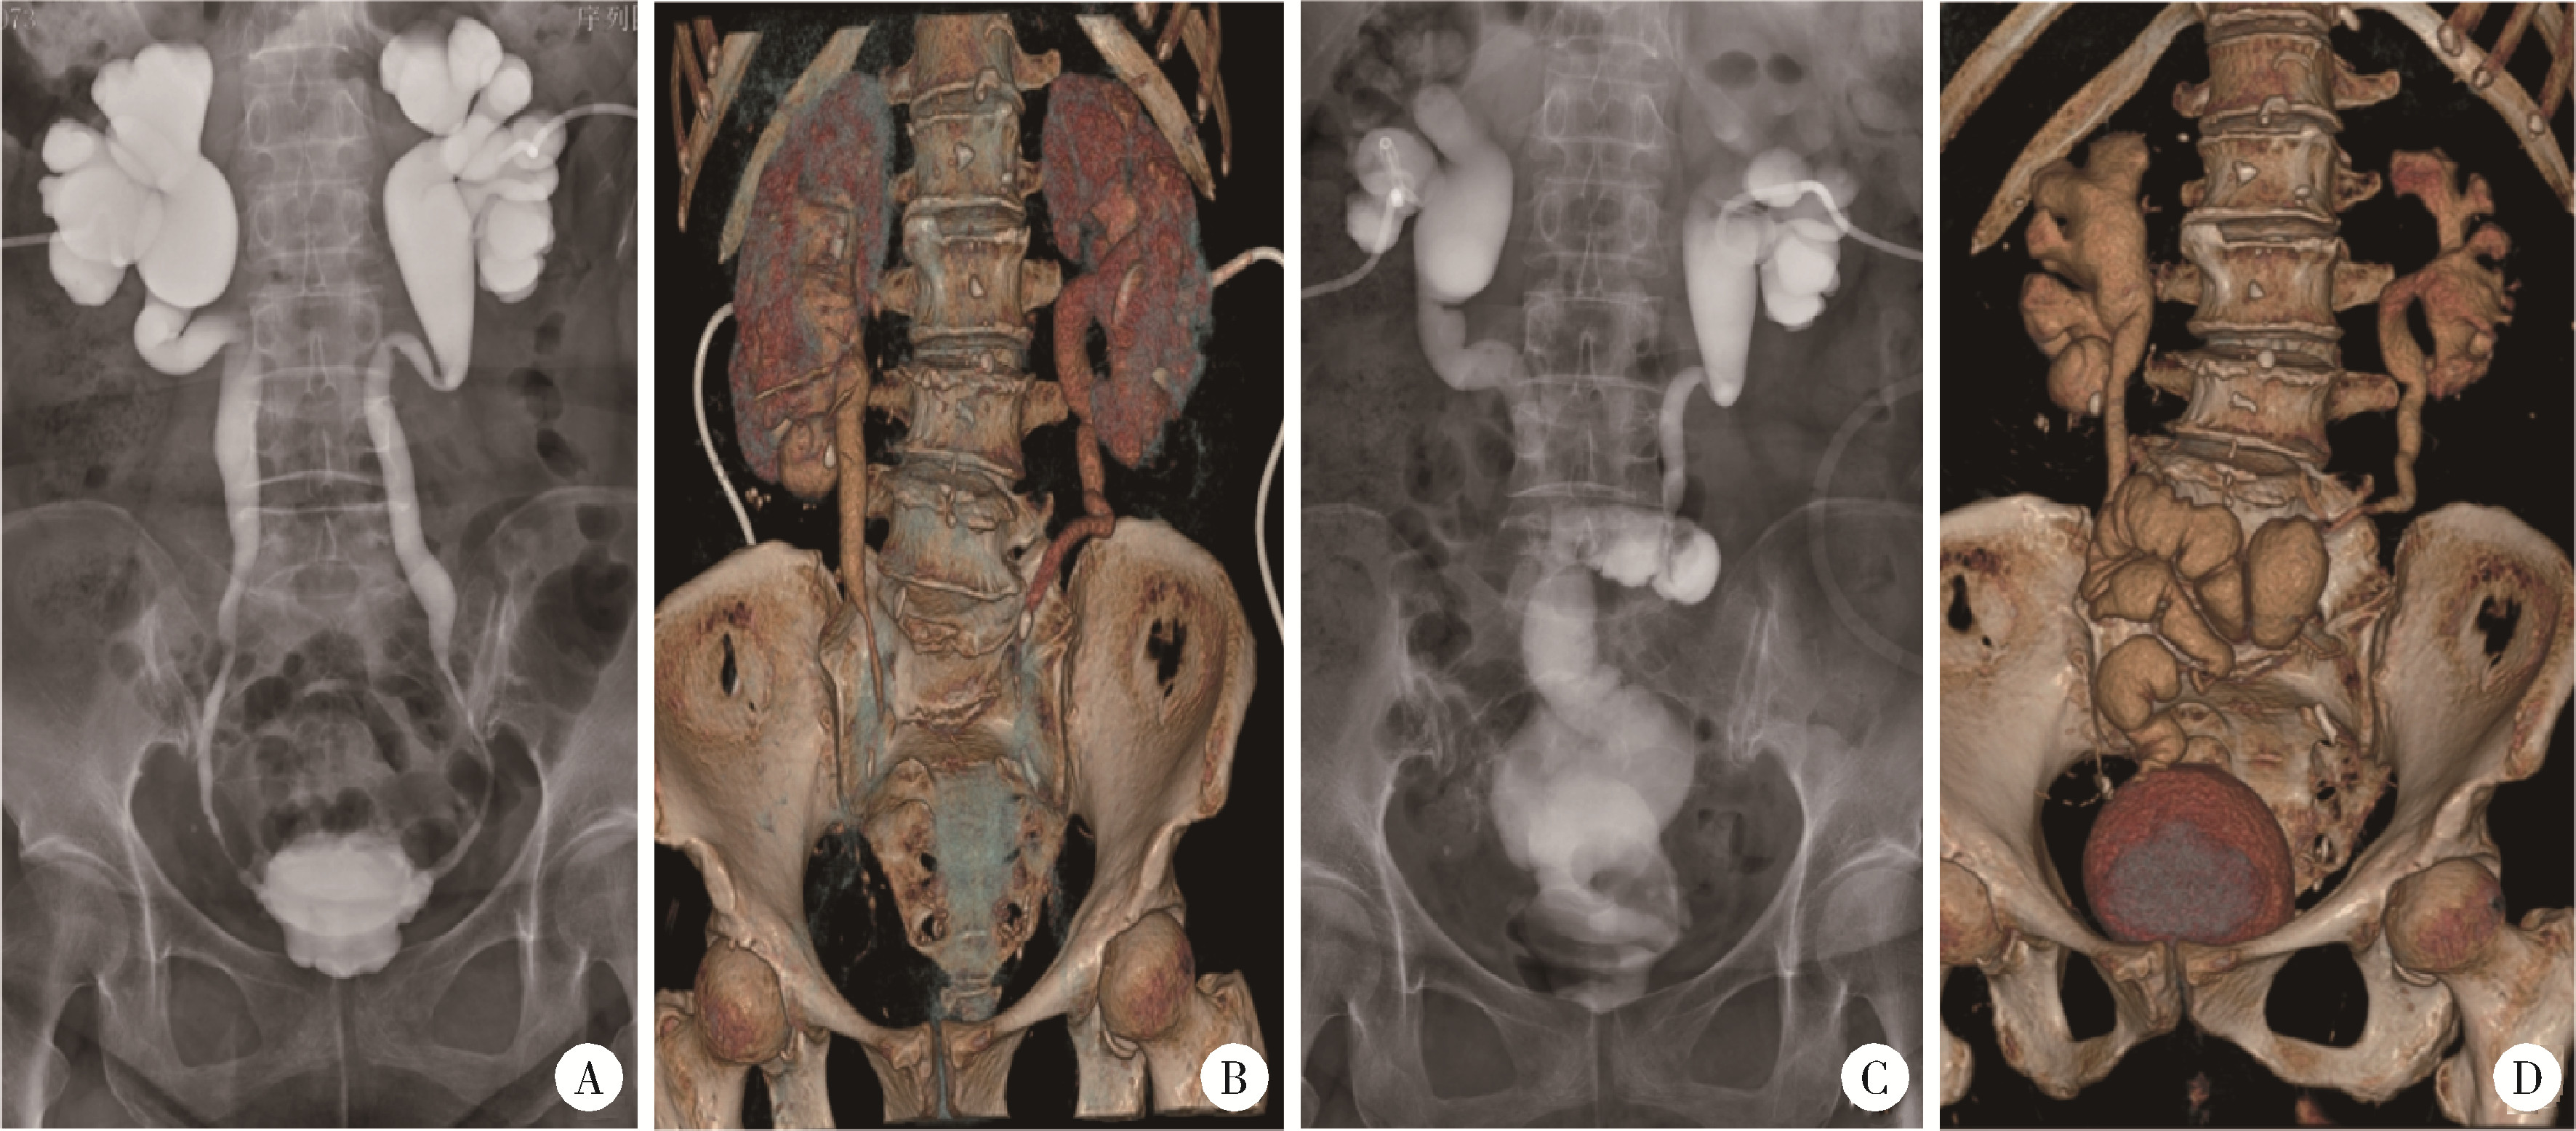

图3 术前及术后影像学检查Figure 3 Preoperative and postoperative imaging examinations A and B, preoperative nephrostogram and 3D CT reconstruction demonstrated bilateral long-segment ureteral strictures, contracted bladder with reduced capacity, and rigid, thickened bladder walls; C and D, two-month follow-up 3D CT reconstruction revealed good peristalsis in the ileal ureteral substitute segment. The bladder exhibited symmetrical morphology with smooth wall contour. |